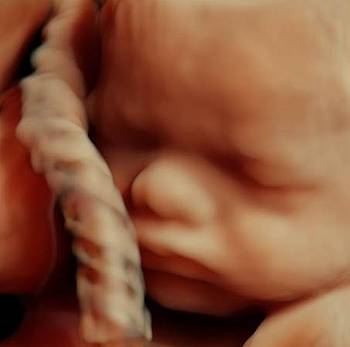

Die Untersuchung ist eine Kombination aus einer Ultraschalluntersuchung (First-Trimester-Screening) mit Darstellung von Nackentransparenz, Nasenbein und anderer Ultraschallmarker kindlicher Chromosomenstörungen, sowie einer Bestimmung zweier Hormone im mütterlichen Blut:( APP-A und freies ß-HCG.

Das First-Trimester-Screening mit Nackenfaltenmessung sollte jedoch auch nach einem Harmony Test durchgeführt werden. Denn es können trotz unauffälligem NIPT Test eine erhöhte Nackentransparenz oder andere kindlichen Auffälligkeiten vorliegen. Es muss jedoch nach einem NIPT keine Risikoberechnung und Hormonbestimmung mehr durchgeführt werden.

Beim First-Trimester-Screening werden folgende Strukturen untersucht: